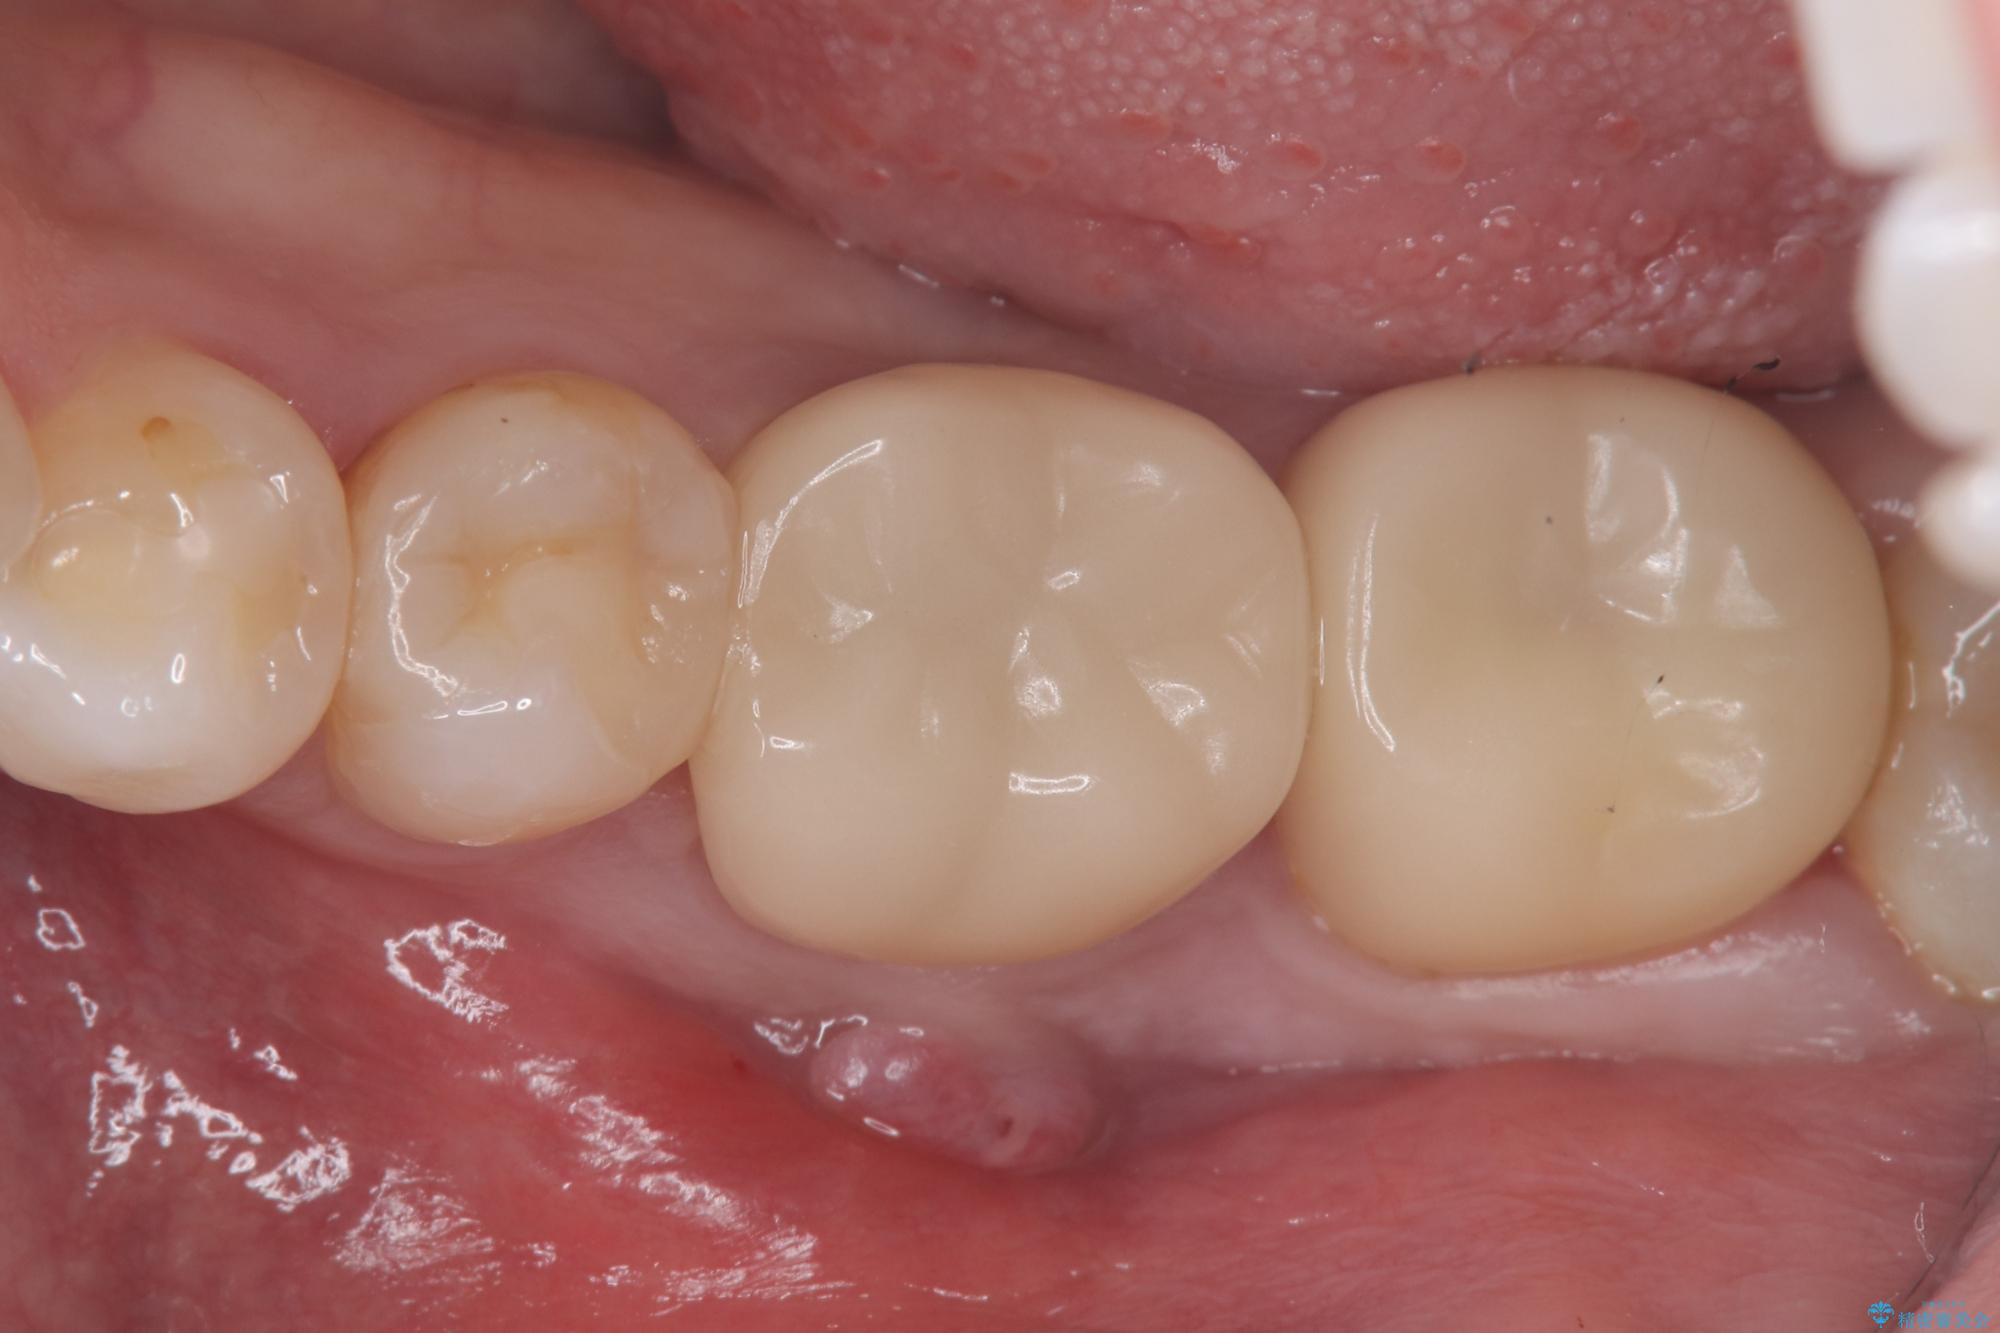

保存が難しい左下6番目の歯を抜歯し、左下8番目の歯(親知らず)を抜歯窩に移植しました。歯牙移植後の動揺防止のため暫間固定を行っています。

また移植後2週間経過時点で根管処置が必要となります。

骨との定着を確認し、今後矯正治療を行う予定のためレジン冠をセットしています。